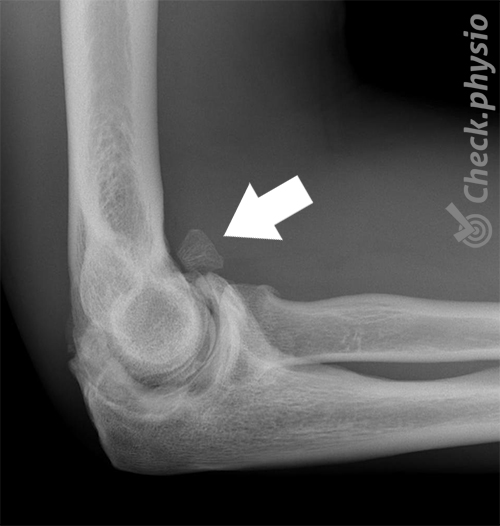

Myositis ossificans Beindannelse i en muskel

Når det dannes bein i en muskel, kalles det myositis ossificans. Dette er som regel et resultat av en muskelskade der en blodutredelse omdannes til benvev. En stor blodutredelse etter en muskelskade fører til myositis ossificans i 10 til 20 % av tilfellene.

Myositis ossificans er en tilstand der en muskelskade fører til lokal dannelse av benvev i den aktuelle muskelen. Etter et (alvorlig) slag oppstår det en blodutredelse i muskelen. Kroppen reagerer ved å sette i gang en betennelsesreaksjon i muskelen (myositt). Det kan føre til varme, rødhet, smerte og hevelse. Denne reaksjonen bidrar til reparasjon og opprydning av blodutredelsen. Vanligvis skjer dette raskt og symptomene forsvinner i løpet av noen uker. Men ikke ved myositis ossificans. Her forkalkes blodutredelsen og et lite bein dannes. Dette kalles ossifikasjon.

Behandlende lege eller fysioterapeut vil stille spørsmål om problemet. Ved myositis ossificans oppstår symptomene som oftest etter en muskelskade som ikke bedres innen to uker. Ved klinisk undersøkelse er det en hard, smertefull kul i muskelen og nedsatt bevegelighet i leddet/leddene muskelen passerer. På et tidlig stadium viser ikke et røntgenbilde noen unormale funn, men etter tre til fire uker blir tilstanden synlig. En ultralyd kan oppdage tilstanden tidligere.